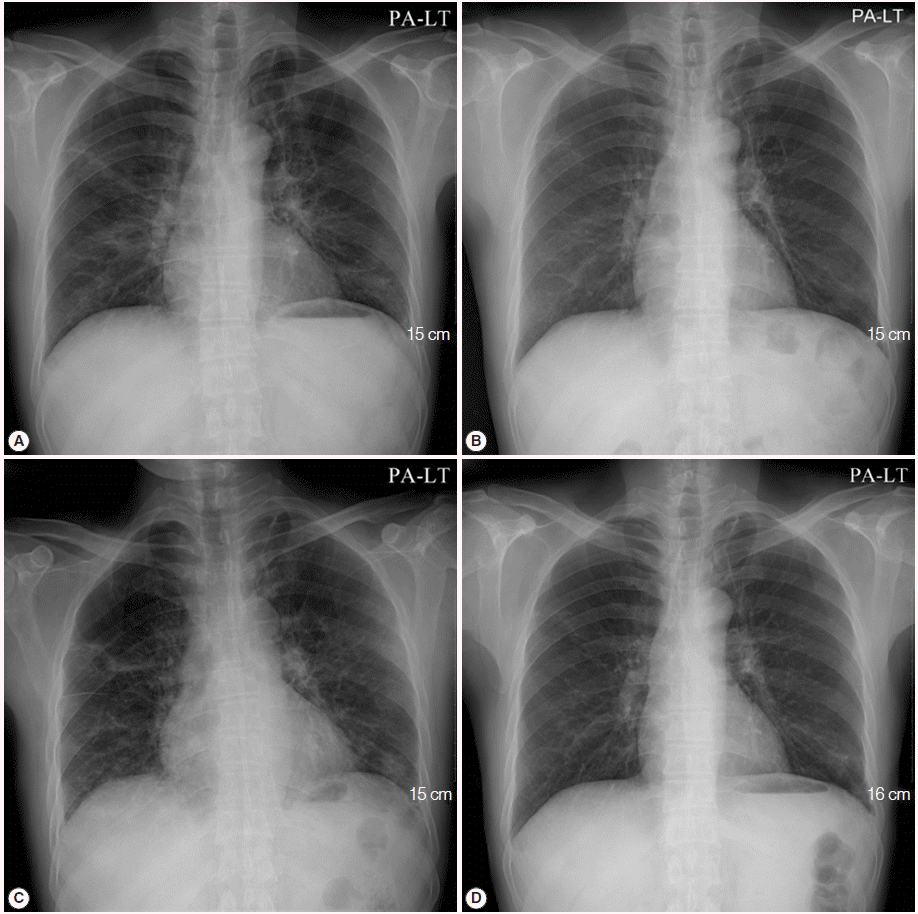

A 50-year-old male visited the outpatient clinic and complained of fever, poor oral intake, and weight loss (6 kg loss in 2 months). Routine laboratory tests and a chest X-ray were performed. Complete blood counts revealed mild leucopenia (WBC 3,720/μl), mild anemia (Hb 11.2 g/dl), and mild eosinophilia (830/μl), however, a normal platelet level (246,000/μ) was observed. Liver function tests showed elevated liver enzymes (AST 61 IU/L, ALT 74 IU/L, and GGT 215 IU/L), and serologic studies for hepatitis B virus, hepatitis C virus, human immunodeficiency virus (HIV), and syphilis were negative. A routine chest X-ray yielded streaky and fibrotic lesions in both lungs (Fig. 1A), which led to further evaluation using contrast chest computed tomography (CT). The chest CT revealed multifocal peribronchial patchy ground-glass opacities in both lungs with septated cystic lesions in the left upper lobe, and the right lower lobe (Fig. 2A, B).

TMP-SMX treatment continued to be administrated for additional 17 days following the patient’s discharge from the hospital. However, the patient complained of cough again, and a follow-up chest X-ray showed aggravation of the streaky and fibrotic lesions in both lungs (Fig. 1C). The patient was readmitted to the hospital, and chest CT was rechecked. A follow-up chest CT revealed an aggravation of multifocal peribronchial ground-glass opacity and septated cystic lesions in both upper lungs, and a newly appeared consolidation in the left lower lobe (Fig. 2C, D). P. jirovecii was clinically suspected to be resistant to TMP-SMX, and molecular studies carried out using PCR with primers Dp15 (5´-TCTGAATTTTATAAAGCGCCTACAC-3´) and Dp800 (5´-ATTTCATAAACATCATGAACCCG-3´) demonstrated mutations at codons 55 and 57 of the dihydropteroate synthase (DHPS) gene as a previous report [12].

Fig. 2.

Initial chest CT revealed multifocal, peribronchial patchy ground-glass opacities in both lungs with septated cystic lesions (arrow) in the left upper lobe (A), and the right lower lobe (B). A follow-up chest CT revealed the aggravation of multifocal, peribronchial ground-glass opacity, and septated cystic lesions (arrows) in both upper lungs (C), and the newly appeared consolidation (arrow) in the left lower lobe (D).

Fig. 2. Initial chest CT revealed multifocal, peribronchial patchy ground-glass opacities in both lungs with septated cystic lesions (arrow) in the left upper lobe (A), and the right lower lobe (B). A follow-up chest CT revealed the aggravation of multifocal, peribronchial ground-glass opacity, and septated cystic lesions (arrows) in both upper lungs (C), and the newly appeared consolidation (arrow) in the left lower lobe (D).